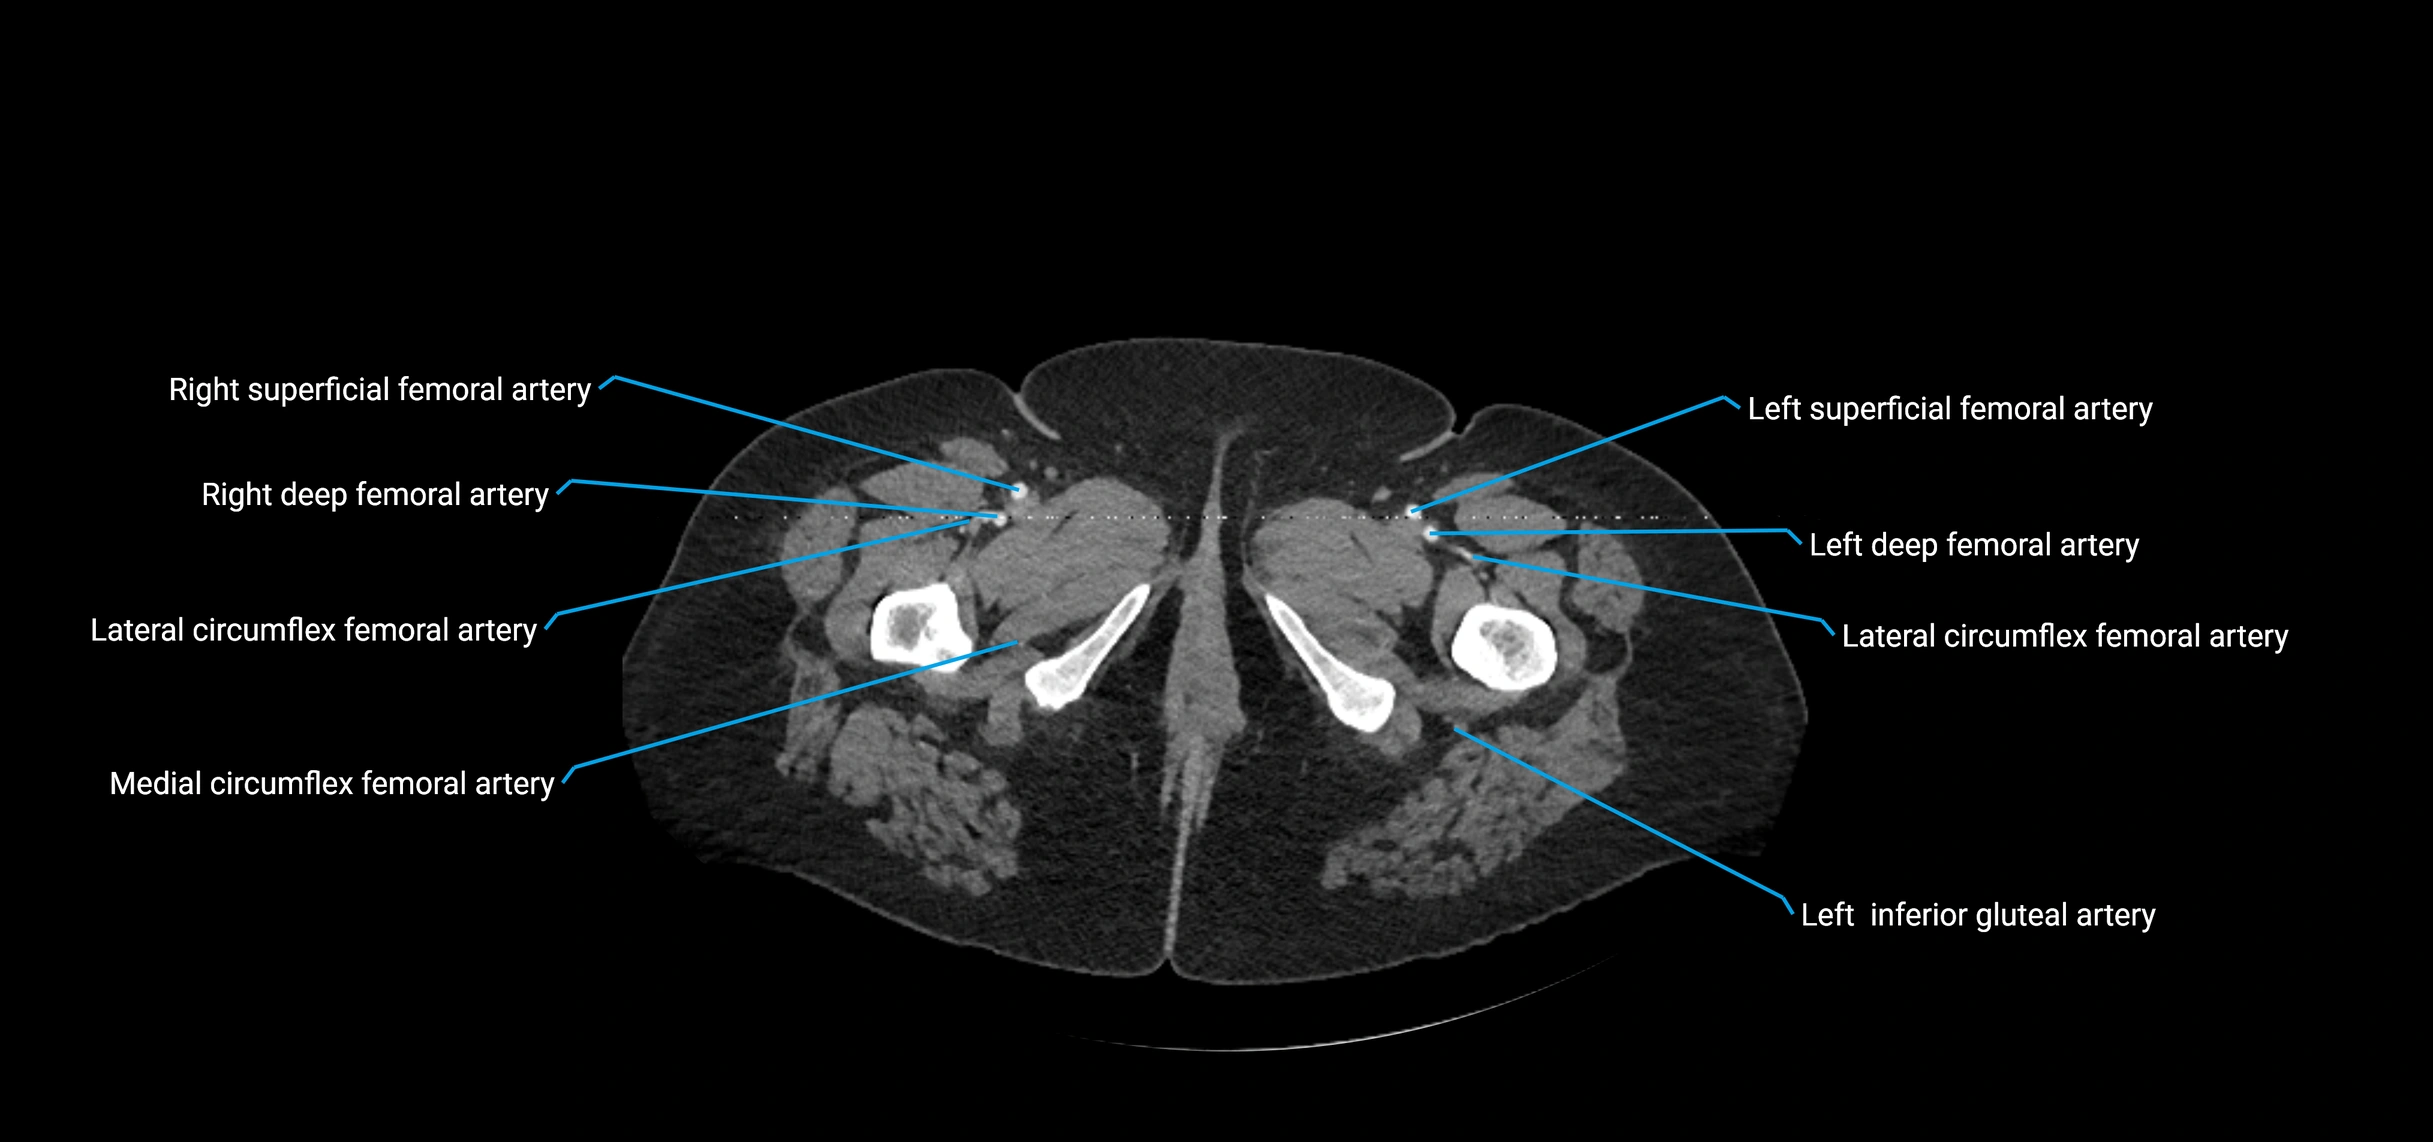

CT images

image

Contrast-enhanced CT (CTA):

• Gold standard for abdominal aortic imaging

• Provides excellent detail of lumen, wall, aneurysm, thrombus, and branch vessels

• Multiplanar and 3D reconstructions help in aneurysm measurement, stent graft planning, and dissection evaluation